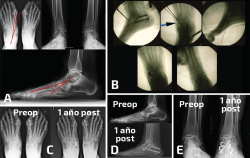

Figura 3. Paciente con mucho dolor en tobillo y región lateral del pie 2 años después de una artrodesis talonavicular por una artropatía postraumática. A: la radiología en carga evidencia una consolidación en varo de la artrodesis, con la columna medial encima (y no al lado) de la lateral, con un callo en el cuarto metatarsiano por lesión de estrés secundaria a la carga anómala; B: osteotomía correctora desrrotatoria en CORA (center of rotation of angulation) talonavicular para conseguir un pie plantígrado. La utilización de 2 agujas permite con facilidad la rotación en el foco de la osteotomía y la orientación espacial de la corrección.

- Demasiado varo: las dobles/triples artrodesis tarsianas son cirugías complejas en las que no es fácil obtener una posición adecuada en el espacio para que el pie funcione plantígrado. El varo iatrogénico es más frecuente que el valgo. Una doble/triple consolidada en varo provocará el daño distal hacia la región lateral del antepié con el resultado de lesiones de estrés sobre el cuarto y el quinto metatarsianos. También existirá una compensación proximal que tendrá que asumir el tobillo que, con frecuencia, presentará dolor medial por sobrecarga y (en ocasiones) inestabilidad anterolateral. El fracaso para diagnosticar el origen de la deformidad en la artrodesis con una consolidación viciosa puede llevar a realizar gestos quirúrgicos erróneos que empeoren mecánicamente el pie. La identificación de un varo en la artrodesis puede verse en la exploración, con un buen análisis visual de la marcha y con el estudio de las queratosis laterales en la región distal y lateral del pie. Unas buenas radiografías en carga nos revelarán muchas pistas directas e indirectas para poder llegar al diagnóstico. Las directas incluyen la apertura del seno del tarso, la posición ortogonal de la subtalar posterior respecto del suelo, la situación de la columna medial del pie encima (y no al lado) de la columna lateral, la visualización completa del cuboides, etc. Las indirectas pueden verse en forma de lesiones sobre el antepié, como la existencia de un callo de fractura en un metatarsiano lateral que nos haga pensar en una fractura de estrés previa por la sobrecarga anterolateral del pie. El tratamiento de esta situación iatrogénica pasaría por la realización de una osteotomía desrrotatoria y la fijación en un valgo discreto mecánicamente adecuado para dejar de sobrecargar el antepié y el tobillo, lo que suele conllevar una mejoría sintomática en el tobillo (Figura 3).